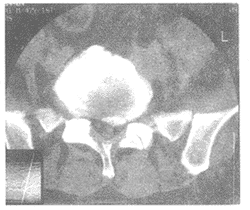

4.CT及CT脊髓造影

髓內腫瘤CTM(脊髓CT造影)多表現為脊髓局限性增大,蛛網膜下腔狹窄或消失,腫瘤密度均一、低密度或等密度、與正常脊髓界限不清;髓外硬脊膜內腫瘤CTM多表現為腫瘤所在部位的充盈缺損,脊髓受壓變形向對側移位,腫瘤上、下的蛛網膜下腔擴大,可有椎間孔擴大、椎管擴大和相鄰椎弓根破壞,可有從椎間孔伸至椎管外的腫瘤陰影或腫瘤鈣化;硬脊膜外腫瘤表現為軟組織影,有強化和鄰近骨質不規則破壞;脂肪瘤表現為不規則分葉狀低密度,無強化。